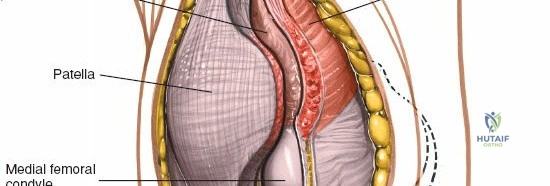

* Patella: The largest sesamoid bone, critical for extensor mechanism efficiency. Its posterior articular surface is covered by hyaline cartilage.

Deep to the extensor mechanism lies the joint capsule, which is continuous with the periosteum of the distal femur and proximal tibia. The capsule forms the suprapatellar pouch proximally, a crucial area for exposure and débridement. The synovial membrane lines the inner surface of the capsule and extends into the joint, forming the intra-articular fat pad (Hoffa's fat pad) distal to the patella.

Once the arthrotomy is complete, the patella is typically everted laterally or subluxated to gain full access to the trochlear groove, femoral condyles, tibial plateau, and menisci.

* Traditional Approach (Patellar Eversion): The patella is gently grasped and everted laterally, typically by flexing the knee to facilitate this maneuver. This provides excellent visualization of all compartments.

Full patellar eversion, offering wide access to the intra-articular structures of the knee, including the femoral condyles and tibial plateau.

- With the patella everted, the suprapatellar pouch is accessible. This is often adherent in osteoarthritic knees and requires sharp dissection to release adhesions and fully visualize the distal femur.

- The fat pad (Hoffa's fat pad) lies anterior to the intercondylar notch. It may be partially resected if it obstructs visualization, though excessive resection can contribute to anterior knee pain.

- Retractors are strategically placed to maintain exposure of the femoral condyles, tibial plateau, menisci, and cruciate ligaments.

Detailed view of the exposed knee joint after patellar eversion. The menisci, articular cartilage, and cruciate ligaments are visible.